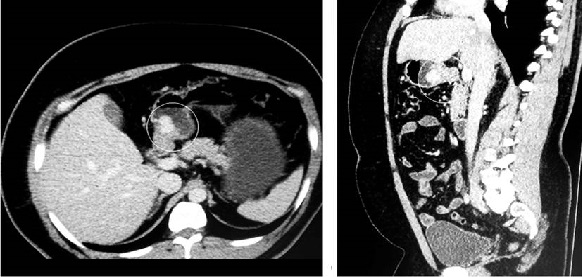

Se trata de un hombre de 35 años que consultó por un cuadro de dolor epigástrico de 6 meses de evolución, con una pobre modulación con analgésicos convencionales e inhibidores de la bomba de protones (IBP), asociado con episodios de lipotimia en varias oportunidades desde el inicio del cuadro y con antecedente de obesidad mórbida y apnea del sueño. Su examen físico estuvo dentro de límites normales. Se le realizó inicialmente una esofagogastroduodenoscopia y una tomografía axial computarizada (TAC), en las cuales se evidenció una lesión de aspecto tumoral de 2 cm a nivel de la cara posterior del antro (Figura 1). Posteriormente, se le solicitó biopsia por ultrasonografía endoscópica (USE), en la cual se evidenció una lesión subepitelial dependiente de la capa muscular que podría corresponder a un GIST.

Con dichos hallazgos, la paciente fue llevada a una antrectomía con reconstrucción en Y de Roux por laparoscopia sin vaciamiento ganglionar (pues las características intraoperatorias sugerían más probablemente un GIST) y se describió como hallazgo intraoperatorio la presencia de un tumor de localización antropilórica.

Las imágenes por TAC se caracterizan por ser lesiones solitarias hipervascularizadas en la fase arterial y persisten en la fase venosa19. Como lo describe Chabowski y colaboradores, estos tumores suelen localizarse en la curvatura menor o mayor y en la región prepilórica con un tamaño promedio de 1-4 cm, con una histología que identifica un endotelio vascularizado rodeado de células tumorales con un núcleo no definido y abundante citoplasma; se diferencian de los tumores carcinoides por ser positivos para vimentina y actina del músculo liso, y por ser negativos para cromogranina7, lo que se correlaciona con los hallazgos histológicos de la pieza quirúrgica de la primera paciente.